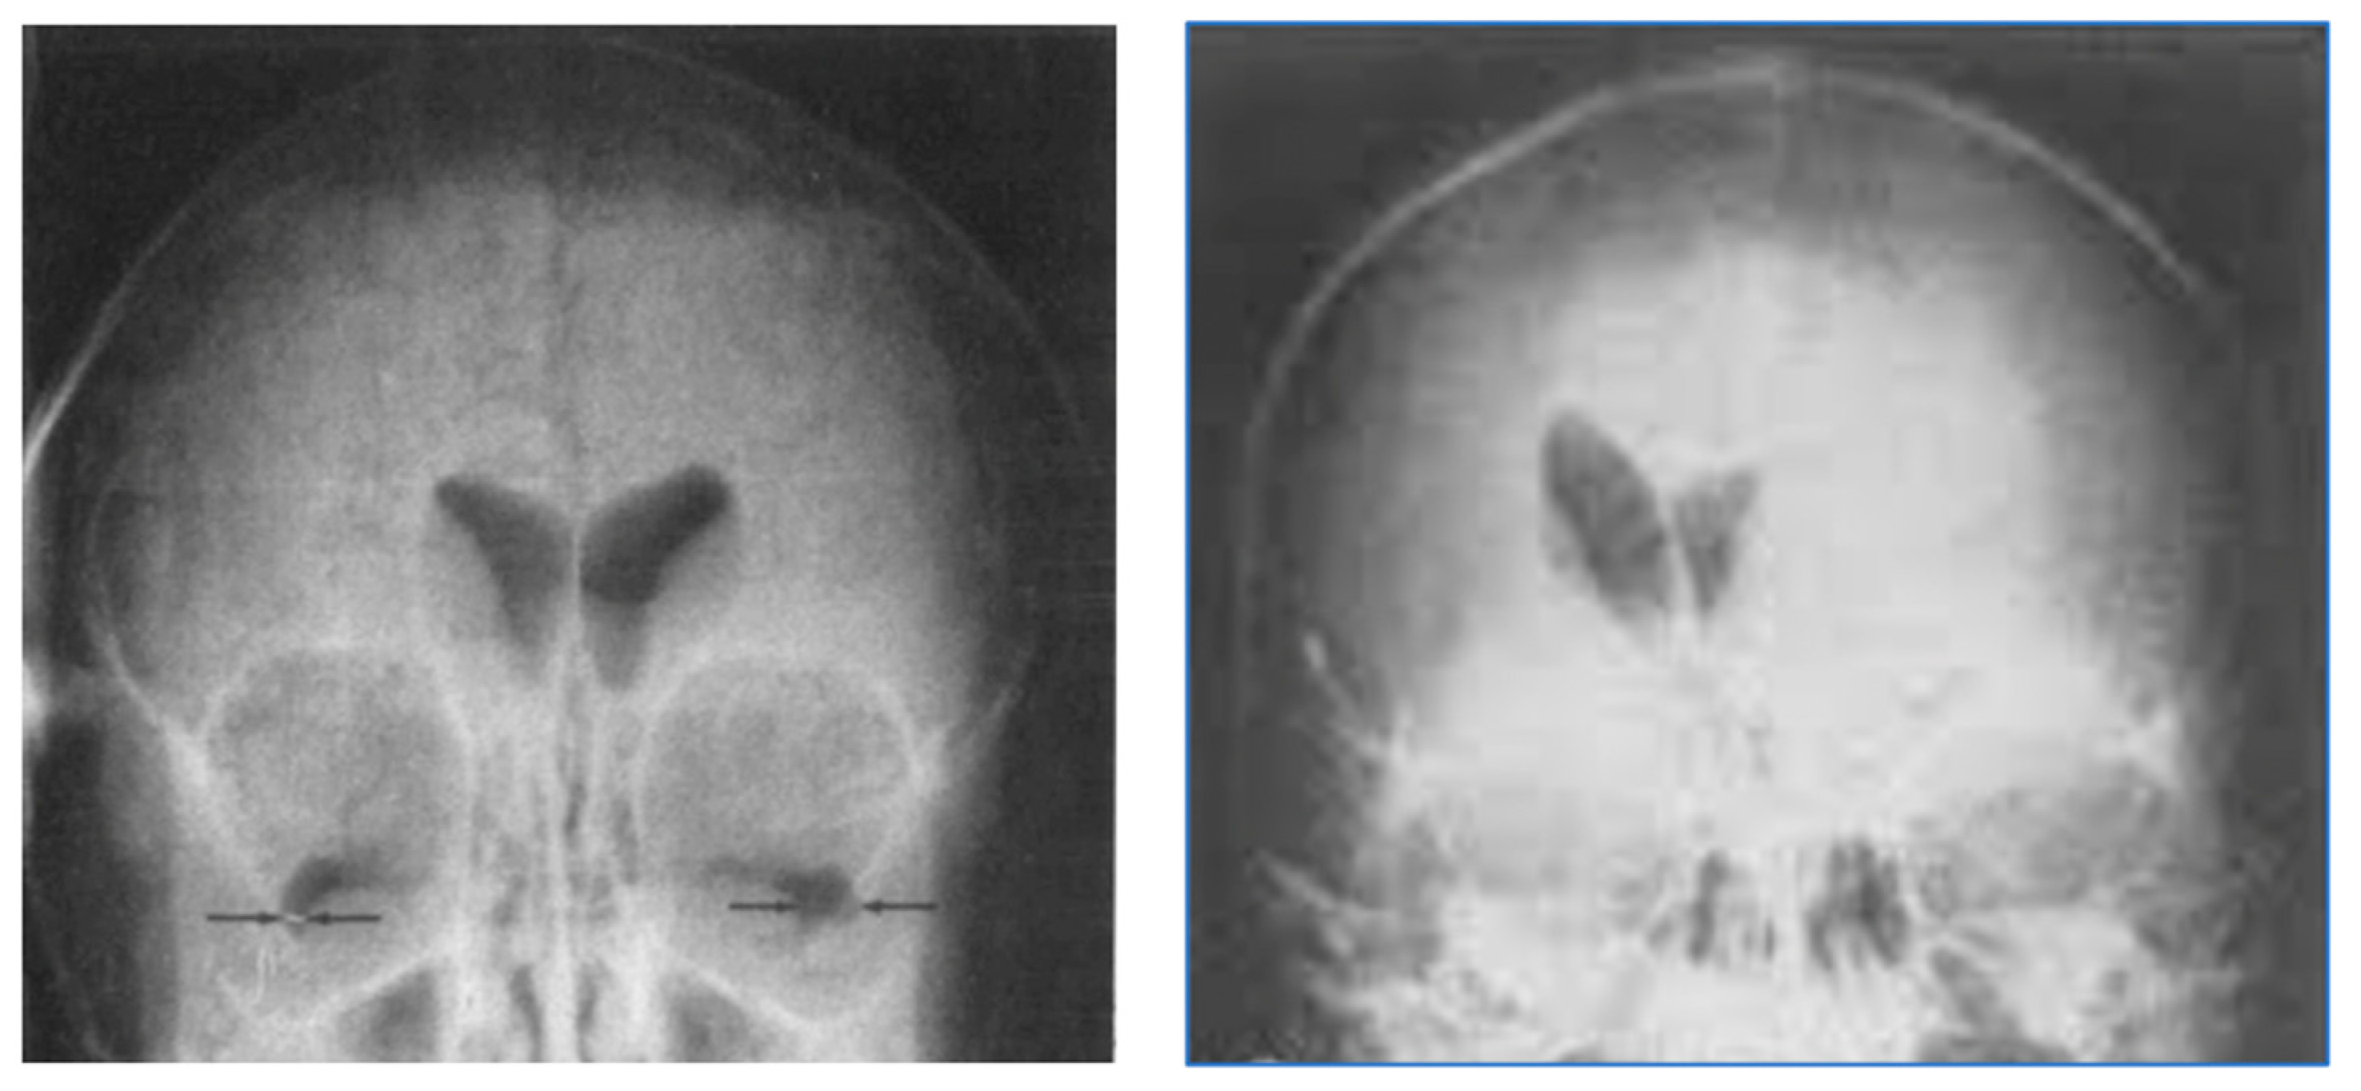

In plain radiographs of the head, contrast could be seen between bone of different thickness, but the soft tissue of the brain itself could not specifically be seen (Figure 2). If air was substituted for CSF, contrast could be created between the ventricular system (now containing air rather than CSF) and the surrounding brain. This technique, which was developed by Walter Dandy in 1918–1919, was used diagnostically to recognize disease of the brain by displacement or distortion of the ventricular system and/or subarachnoid space in air studies of the brain [2,3] as shown in Figure 3.

Figure 3.

Air studies, frontal views. Normal control (left) and patient with brain tumor in the left cerebral hemisphere (right). The CSF in the ventricular has been replaced by air. The air has a low signal (black appearance) and this creates contrast between the ventricular system and surrounding brain. In the normal air study on the left, the lateral ventricles are symmetrical. In the patient on the right both lateral ventricles are displaced to the right by a tumor in the left hemisphere (black arrow). There is encroachment of the brain into the left lateral ventricle and probable enlargement of the right lateral ventricle.